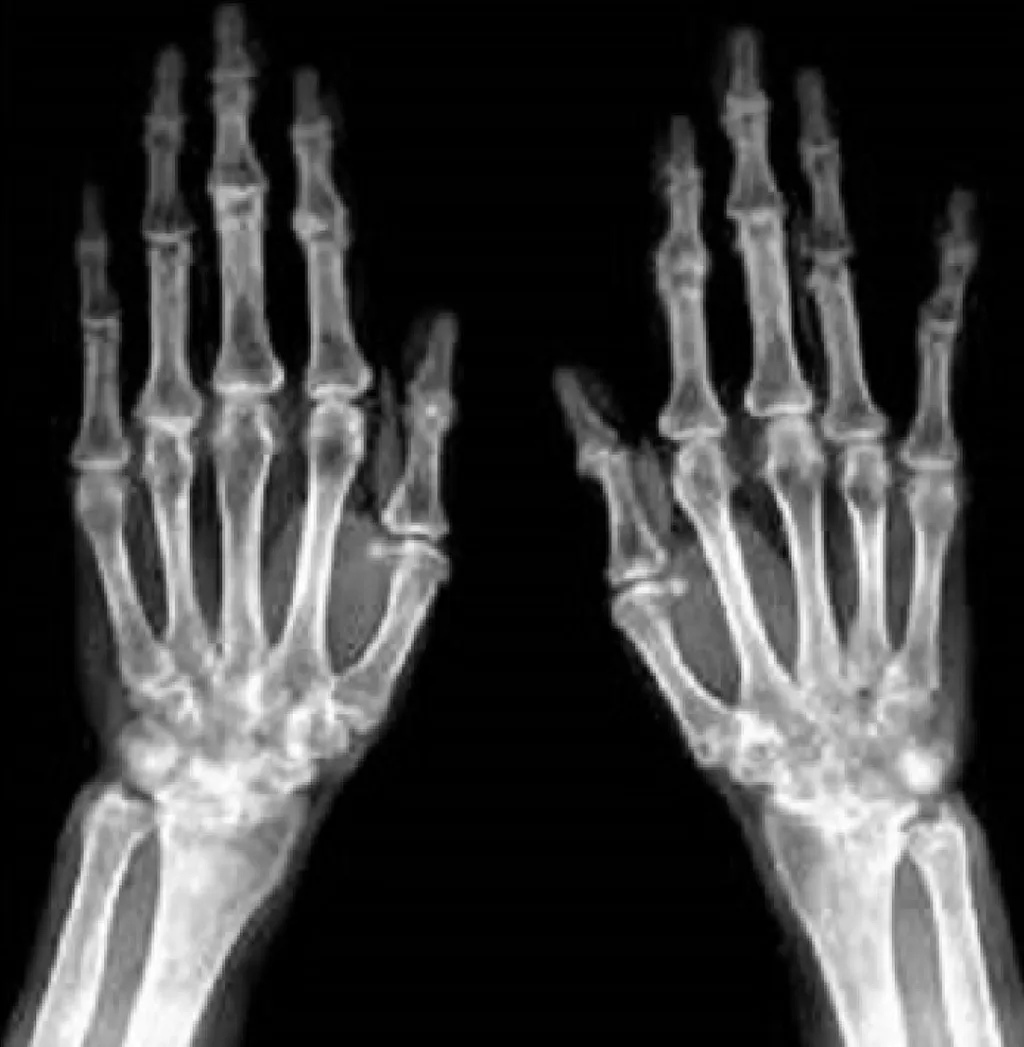

【113-2 醫學(五) 第74題】57歲女性雙手多處關節腫痛,雙手X光檢查如附圖,最可能的診斷為何?